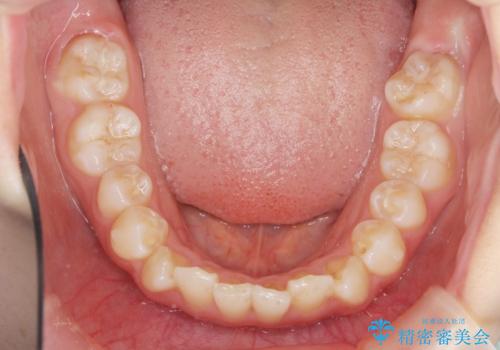

インビザラインライトで行う短期マウスピース矯正治療

- 前歯のガタつきを並べたいたいと、矯正治療を希望され来院されました。

とにかく短期間で前歯だけの治療を行いという希望が強く、全体矯正と前歯だけの部分矯正の仕上がりのイメージを確認したのち14枚のマウスピースで前歯のみの矯正治療を行っていくこととしました。

インビザラインライトは軽度なガタつきや傾斜の改善に用いられる全14枚のマウスピース矯正です。